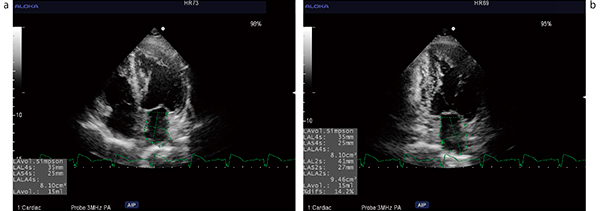

図4 セミオートによる左房容量計測結果

a:左房容量計測(4腔断面)

b:左房容量計測(2腔断面)